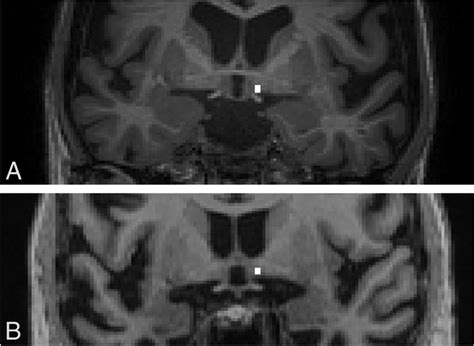

One notable study published in the Journal of Neuroscience investigated the effects of deep brain stimulation (DBS) on the BNM in animal models of Alzheimer's disease. The results showed that DBS could improve cognitive function by enhancing cholinergic activity in the BNM and its target regions. This finding highlights the potential of neuromodulation techniques as a therapeutic approach for BNM-related disorders.

One innovative therapeutic approach is the use of deep brain stimulation (DBS) to modulate BNM activity. DBS involves implanting electrodes in the brain to deliver electrical impulses that can enhance cholinergic function and improve cognitive performance. While still experimental, DBS holds promise as a targeted treatment for BNM-related disorders.